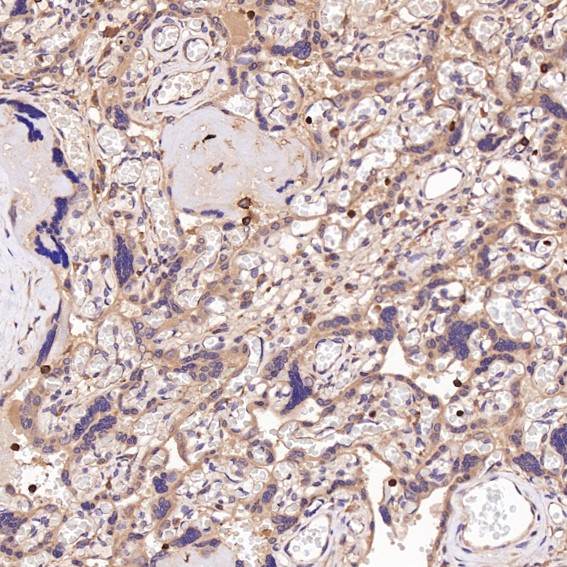

Immunohistochemical analysis of paraffin-embedded Mouse lung, using the Antibody.